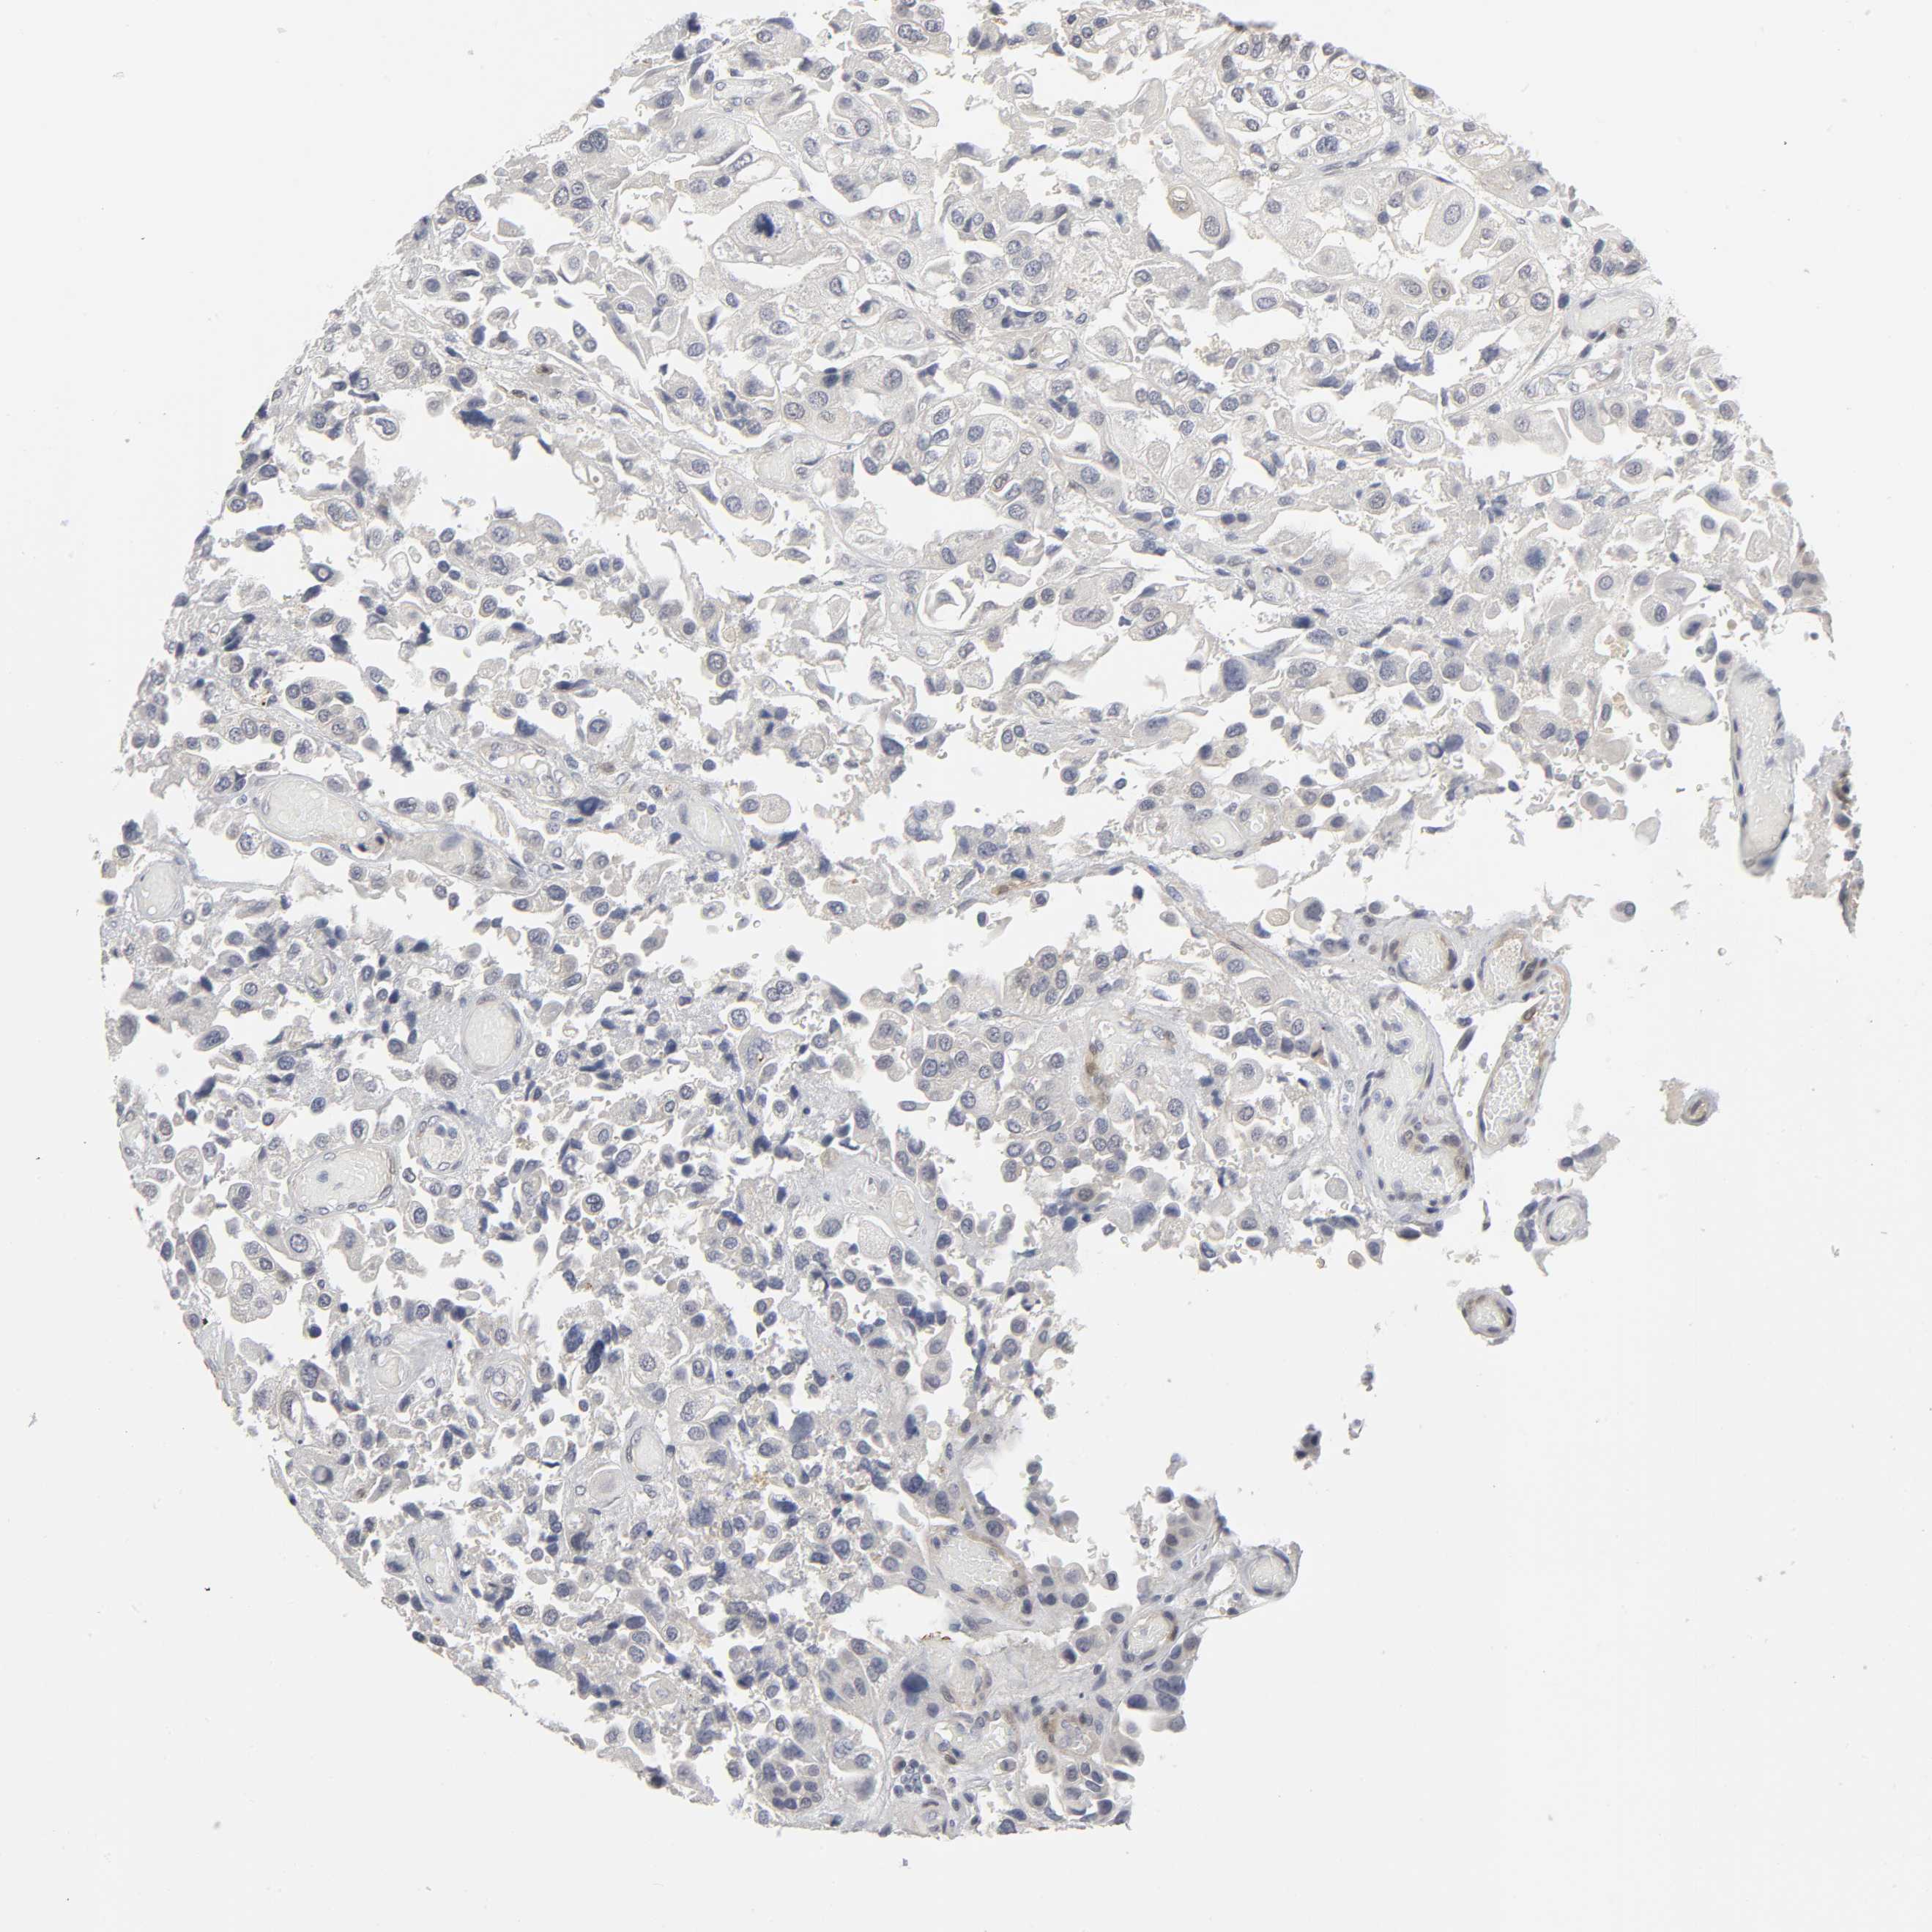

UROTHELIAL CANCER - Protein expressioni

A mouse-over function shows sample information and annotation data. Click on an image to view it in a full screen mode. Samples can be filtered based on level of antibody staining by selecting one or several of the following categories: high, medium, low and not detected. The assay and annotation is described here.

Note that samples used for immunohistochemistry by the Human Protein Atlas do not correspond to samples in the TCGA dataset.

Antibody stainingi

Antibody staining in the annotated cell types in the current human tissue is reported as not detected, low, medium, or high, based on conventional immunohistochemistry profiling in selected tissues. This score is based on the combination of the staining intensity and fraction of stained cells.

Each image is clickable and will lead to virtual microscopy that enables deeper exploration of all samples and also displays staining intensity scores, fraction scores and subcellular localization as well as patient and tissue information for each sample.

Antibody HPA004749

Staining

High

Medium

Low

Not detected

Intensity

Strong

Moderate

Weak

Negative

Quantity

>75%

75%-25%

<25%

None

Location

Nuclear

Cytoplasmic/membranous

Cytoplasmic/membranous,nuclear

Urothelial carcinoma, High grade

Urothelial carcinoma, Low grade